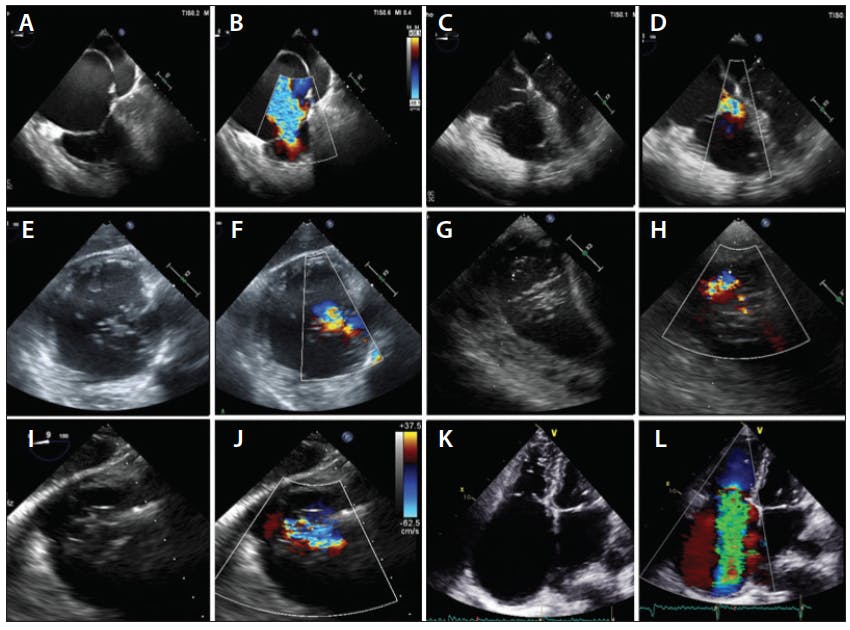

Table 2 summarizes the current evidence and expert opinions on when a specific TTVI approach is or is not preferred.8,18,20,21,23,27,28 Furthermore, Figure 3 shows examples of primary and functional TR, different TR jet locations, and an example of a large coaptation gap in a patient with torrential TR. Because no randomized controlled trials are currently available to build recommendations for the use of TTVI, patient selection remains in the hands of experienced and dedicated heart teams on a case-by-case basis. The promising initial results observed with different interventional methods have generated a vast interest in the use of TTVI on a larger scale, and further research is needed to clarify the role of transcatheter interventions in the setting of severe TR.

Figure 3. Functional TR due to right atrial dilatation (A, B) compared with primary TR due to leaflet prolapse (C, D). Examples of TR jet location on a transgastric view on TEE with a central to anteroseptal (E, F), posteroseptal (G, H), and anteroposterior (I, J) jet location. Example of a patient with functional torrential TR due to right atrial dilatation with a large coaptation gap of approximately 10 mm (K, L).